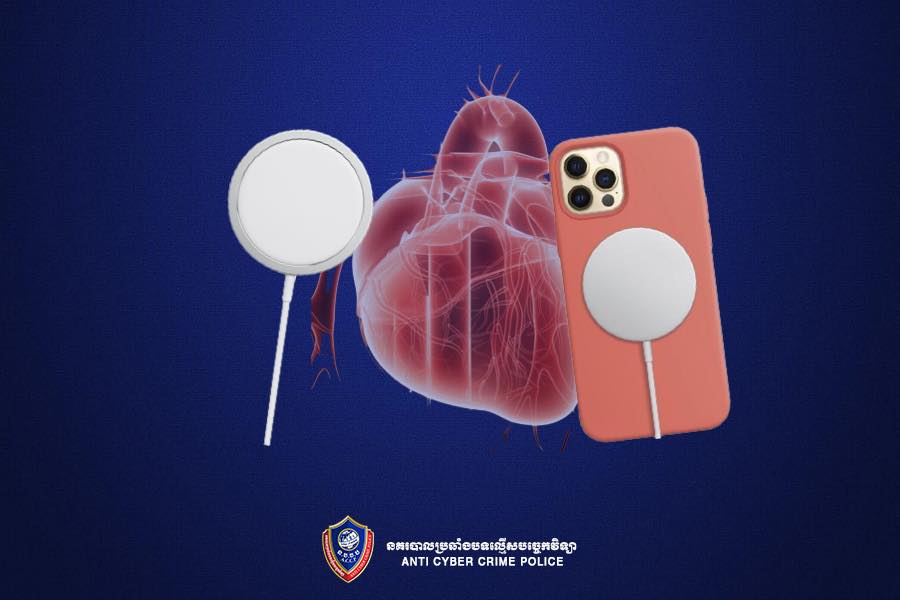

យោងតាមការបញ្ជាក់ពី នាយកដ្ឋានប្រឆាំងបទល្មើសបច្ចេកវិទ្យា បានឲ្យដឹងថា នៅពេលដែលក្រុមហ៊ុន Apple បានធ្វើការប្រកាសនូវទូរសព្ទ iPhone 12 កាលខែតុលា ក្រុមហ៊ុនបានទទួលស្គាល់ថា សារធាតុឆក់នៅក្នុងទូរសព្ទជំនាន់ថ្មីនេះ អាចធ្វើឱ្យប៉ះពាល់ដល់ដំណើរការរបស់ឧបករណ៍រំញោច ឬជំនួយបេះដូងមានដូចជា Pacemaker និង Defibrillator។

ប៉ុន្តែនៅពេលថ្មីៗនេះក្រុមហ៊ុនបានបន្ថែមពាក្យពេចន៍មួយចំនួនទៀតដើម្បីបញ្ជាក់ឱ្យកាន់តែច្បាស់ពីការប៉ះពាល់នេះ បន្ទាប់ពីវេជ្ជបណ្ឌិតមួយចំនួននៅរដ្ឋ Michigan បានធ្វើការសាកល្បងដោយដាក់ទូរសព្ទ iPhone 12 និងឧបករណ៍ Defibrillator នៅជិតគ្នាហើយដែលជាលទ្ធផលឧបករណ៍ Defibrillator បានឈប់ដំណើរការណ៍ជាបណ្ដោះអាសន្ននៅក្នុងពេលសាកល្បងនេះ។ បច្ចុប្បន្នក្រុមហ៊ុន Apple បានណែនាំបន្ថែមឱ្យអ្នកប្រើប្រាស់ដាក់ទូរសព្ទ ឬឧបករណ៍ MagSafe ឱ្យបានចម្ងាយយ៉ាងតិច ១៥សង់ទីម៉ែត្រនៅពេលប្រើប្រាស់ ឬ ៣០សង់ទីម៉ែត្រនៅពេលដែលលោកអ្នកកំពុងតែបញ្ចូលថ្ម ពីឧបករណ៍រំញោចបេះដូង។

ដើម្បីសុវត្ថិភាពក្នុងការប្រើប្រាស់របស់លោកអ្នក ក្រុមអ្នកស្រាវជ្រាវក៏បានសំណូមពរឱ្យអ្នកប្រើប្រាស់ដែលមានដាក់ឧបករណ៍រំញោចបេះដូង Pacemaker ឬ Defibrillator នៅក្នុងខ្លួន ចៀសវាងដាក់ទូរសព្ទនៅក្នុងហោប៉ៅអាវខាងលើ ឬនៅលើទ្រូងរបស់លោកអ្នក៕